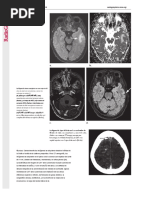

Figura 1: La imagen muestra el sistema de estratificación de riesgo del Sistema de Información y Datos de Reporte de Anexos Ovarianos (O-RADS) MRI. DCE = contraste

dinámico, DWI = imagen de difusión ponderada, N/A = no aplicable, PPV = valor predictivo positivo. Reproducido, con permiso, del Colegio Americano de Radiología.